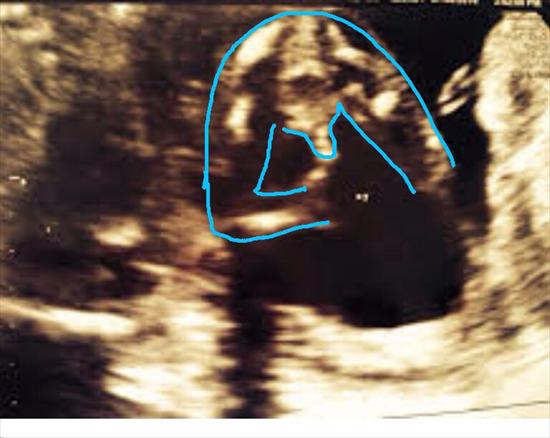

This is the potty shot of my scan 16+4 confirmed boy, but worried that its a mistake and thats actually the umbilical cord? What do you think? I really want a boy!! I already have 3 girls!!!

With the outline it should be clear to everyone that it is a boy... Congrats! I can understand your concern about it being the cord. My DS2 looked the same and I did hope they were wrong but it was confirmed several times after that. If you have any doubt maybe you can convince your Dr to do another US in about 3wks and it should easier to see.

with the outline that certainly looks like a boy. Congrats!

Yup with the outline I'd say that's defo a boy! Congrats!